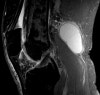

MRI가 필요하지는 않지만, 낭종의 위치와 낭종액의 유형, 다른 관절 속 병변 존재를 알 수 있습니다.

드물게는 synovial sarcoma 등의 악성 종양을 감별해야 하는 경우도 있습니다.

MRI : 베이커 낭종(슬와낭종, Baker's cyst, Popliteal cyst)